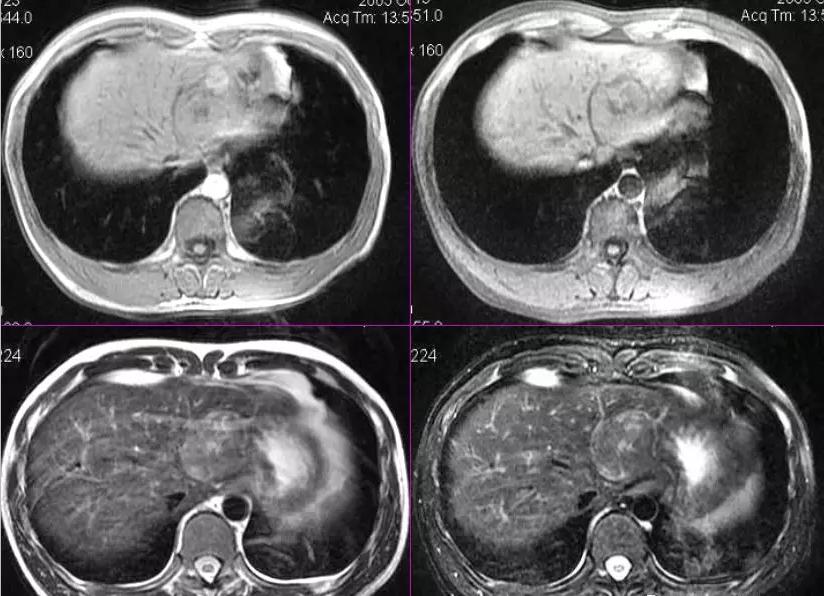

7. CT Scan

CT scan is an important diagnostic method for detecting liver cancer, as it can clearly display the tumor's size, shape, number, and boundaries. Furthermore, through imaging analysis, the various ducts within the liver can be reconstructed, allowing for precise mapping of the relationship between the vessels in each liver segment and the tumor.